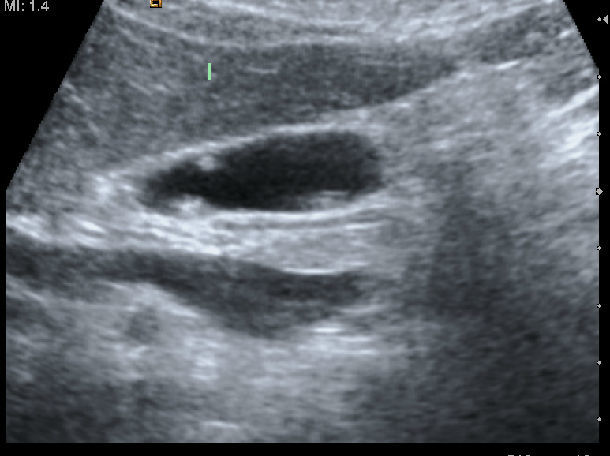

对此病的诊断主要依靠B超,但难以区分是肿瘤性还是非肿瘤性息肉,是良性还是恶性病变。帮助确诊的方法有:常规超声加彩色多普勒超声;内镜超声检查;CT增强扫描;超声导引下经皮细针穿刺活检。一般来说,彩超是最常规也是最实用的啦!

挑一篇有代表性的文献说说吧。英国Giuseppe Garcea博士的一项回顾性分析的研究结果显示:原始直径较大(7mm)的息肉与直径5mm的息肉相比,更容易在随访期间增大(P<0.05)。研究还显示,原始直径大于10mm的息肉更可能是恶性的,或有癌变的可能(曲线下面积0.81,p<0.001)。由于胆囊息肉的罕见性和对其形成原因不完全了解,再加上大部分胆囊息肉倾向于良性的,仅有少数是腺瘤样的,从而导致无法确定最佳的治疗方案。此外,超声诊断胆囊息肉仍有难度,许多诊断为胆囊息肉的其实是胆囊壁的结石或胆固醇性息肉。